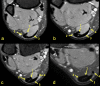

The aim of the study was to check if the subtendons of the Achilles tendon can be identified in vivo on MRI in the midportion of the tendon. The relation of the plantaris tendon to the Achilles tendon was also examined. A retrospective study of 200 MRI of ankle joints including the Achilles tendon was conducted. Statistical analysis of the correlation between the possibility of identifying the subtendons and the side, gender, presence of the central soleus tendon and plantaris tendon variation was performed. The inter-observer agreement between two reviewers in their evaluation of the subtendons was assessed using kappa statistics. The subtendon from the lateral head of the gastrocnemius muscle was identified in 65% (k = 0.63) and was located in the anterior part of the Achilles tendon. The subtendon from the soleus muscle was recognized in 12% (k = 0.75) comprising anterior part of the tendon. In 6% the subtendon from the medial head of the gastrocnemius muscle was identified (k = 0.58). The central soleus tendon was identified in 85% of cases. Statistical analysis shows the weak correlation of the presence of the central soleus tendon and the possibility of identifying the subtendon from the soleus muscle. The plantaris tendon was directly related to the insertion of the Achilles tendon in 42.5%. Identification of the subtendons of the Achilles tendon on MRI is challenging, and most often it is only possible to find the subtendon of the lateral head of the gastrocnemius muscle.